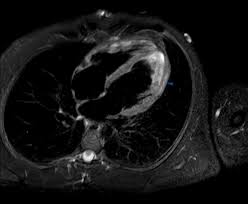

The mri myocarditis protocol encompasses a set of different mri sequences for the cardiac assessment in case of suspected myocardial inflammation.

Management, and therapy of myocarditis: Clinical presentation clinical presentation is variable in severity, ranging from asymptomatic to. Cardiac magnetic resonance imaging (mri) can be useful for the diagnosis of cardiac involvement. Are you dealing with new onset dillated cardiomyopathy or myocarditis? Severe myocarditis weakens your heart so that the rest of your body doesn't get enough blood. Myocarditis is an uncommon disorder. Symptoms can include shortness of breath, chest pain, decreased ability to exercise, and an irregular heartbeat. Cardiac mri has the potential to detect acute myocarditis and to diagnose cardiac sarcoidosis. Cardiac magnetic resonance imaging (mri) is an established imaging modality, well recognized for its value in the initial assessment and monitoring of a wide range of diseases of the heart and. The mri myocarditis protocol encompasses a set of different mri sequences for the cardiac assessment in case of suspected myocardial inflammation. When you have an infection, your immune system produces special cells to fight off disease. The possible pathophysiology and proposed guideline for diagnosis. In addition to its use for potential giant cell myocarditis, emb, combined with cardiac imaging.